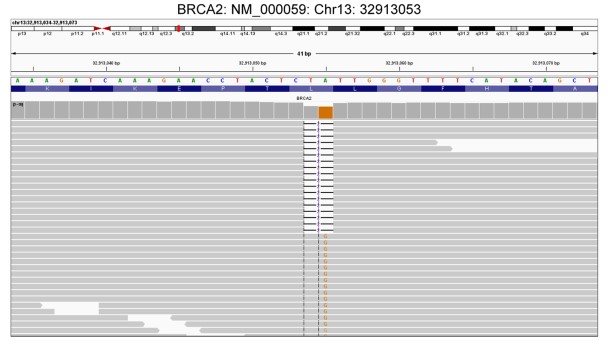

近日,求臻医学与青岛市中心医院放疗科张小涛主任合作,首次报道了一例有BRCA2胚系移码突变(NM_000059.3:exon11: c.4563_4564delAT: L1522fs)的难治性转移性纵隔卵黄囊瘤患者对局部放疗有显著反应。目前该案例报道(case report)已在线发表于Cancer Biology & Therapy(IF:4.742)。 研究背景 卵黄囊瘤,即内胚层窦瘤,是发生在卵黄囊内的高度侵袭性生殖细胞肿瘤。根据位置,可分为性腺卵黄囊瘤和性腺外卵黄囊瘤。性腺外卵黄囊瘤相对少见。它们通常发生在身体的中轴,如大脑、纵隔和腹膜后。纵隔卵黄囊瘤在婴儿期和青春期后更常见。 目前,卵黄囊瘤的标准治疗方案是博莱霉素(Bleomycin)、依托泊苷(Etoposide)和顺铂(Cisplatin)(BEP)化疗后进行手术。然而,由于恶性程度高,诊断时不可能完全切除,原发性纵隔卵黄囊瘤的预后极差,5年生存率为40%-50%,复发后仅仅有6个月的生存期。 过往研究表明,原发性纵隔卵黄囊瘤患者对化疗反应良好,但对放疗反应较差。据报道,某些病例对放射治疗敏感。 然而,目前对原发性纵隔卵黄囊瘤精准放疗的预测性生物标志物尚未被探索。 DNA损伤修复(DDR)对恶性和正常细胞的生存都至关重要。临床前数据显示,辐射敏感性与DDR有关。近期研究表明,DDR基因突变可能预测多种实体瘤患者对放疗敏感性增强。 本案例报告了一例难治性转移性原发性纵隔卵黄囊瘤男性患者。当患者接受化疗,同时使用或不使用特瑞普利单抗(Toripalimab, PD-1抗体)时,疾病进展迅速。然而,该患者对局部放疗很敏感。通过全外显子组测序(WES)在患者体内检测到了BRCA2胚系移码突变。 病例分享 上下滑动查看所有内容 病例讨论 放疗在纵隔卵黄囊瘤的治疗中起着至关重要的作用。为了最大限度地从放疗中获益,探索与疗效相关的生物标志物至关重要。以往的研究证明,包括BRCA1/2在内的DDR基因突变可能会增强多种实体瘤患者的放射敏感性。然而,DDR基因突变作为原发性纵隔卵黄囊瘤放疗的预测性生物标志物尚未被探索。 放射敏感性取决于多种因素,例如肿瘤组织学、辐射剂量和肿瘤细胞的固有放射敏感性等。其中肿瘤细胞的内在放射敏感性是最重要的因素。由于放疗主要通过产生DNA双链断裂(DSB)诱导细胞死亡,DDR无疑会影响肿瘤细胞的放射敏感性。 DDR系统通过八条途径修复多种形式的DNA损伤,以适当保护基因组的完整性。这八条途径包括错配修复(MMR)、碱基切除修复(BER)、核苷酸切除修复(NER)、同源重组修复(HRR)、非同源末端连接(NHEJ)、检查点因子(CPA)、范科尼贫血(FA)和易位DNA合成(TLS)。其中HRR和NHEJ通路负责修复DSB, BER负责修复单链断裂(SSB),MMR通路负责修复DNA插入/缺失。 BRCA1和BRCA2是介导HRR途径的两个关键分子。这两个基因的突变可能会破坏DSB的修复。由于辐射主要通过产生DNA双链断裂诱导细胞死亡, BRCA1或BRCA2突变的恶性肿瘤通常会导致HRR通路的缺陷,因此对电离辐射反应良好。 目前纵隔卵黄囊瘤的标准治疗方案是新辅助化疗后将残余肿块切除术。由于确诊时肿瘤通常巨大且常与邻近器官有纤维粘连,化疗后残余肿瘤的完全切除非常困难,也间接导致了本病较差的预后。新辅助化疗是纵隔卵黄囊瘤的主要治疗方法,初始治疗方案推荐以铂为基础的化疗,常用方案为4-6个周期的VIP(顺铂、依托泊苷和异环磷酰胺)或BEP。含铂方案化疗使高达50%的患者实现了长期生存。我们检索到了许多新辅助化疗后R0切除及术后达到病理学完全缓解(PCR)的报道。对于化疗和手术后复发的纵隔卵黄囊瘤患者,再次化疗的效果很差。本例患者对化疗不敏感,原因尚不明确。 此外,患者对免疫检查点抑制剂(ICI)治疗不耐受。可能与患者MSI-L、TNB-L和HLA LOH强阳性有关(表1)。HLA LOH强阳性意味着HLA-A、B和C三个基因同时缺失。HLA LOH是免疫逃逸的常见原因。这是由于抗原提呈细胞通过HLA I类分子的抗原提呈新抗原在细胞免疫中起着关键作用。HLA-LOH导致抗原呈递减少,从而促进了免疫逃逸。 此前的研究表明,BRCA1突变的携带者患乳腺癌、卵巢癌、前列腺癌和结肠癌的风险增加,而BRCA2突变的携带者患男性乳腺癌、胰腺癌和前列腺癌的风险更高。目前卵黄囊瘤的发病机制尚不清楚。然而,该患者的BRCA2胚系移码突变应该与其病因密切相关。BRCA2胚系突变导致负责DSB修复的HRR通路缺陷。 PARP抑制剂可能抑制PARP-1介导的SSB修复(即BER通路),从而增加DNA链断裂的积累,促进基因组不稳定性和细胞凋亡。根据合成致死率的概念,PARP抑制剂可以有效地摧毁BRCA基因缺陷的肿瘤以及同源重组能力较低的睾丸肿瘤细胞系。迄今为止,FDA已批准奥拉帕利用于治疗BRCA胚系突变的卵巢癌、乳腺癌和前列腺癌。此外,奥拉帕利在治疗BRCA胚系突变的胰腺癌和小细胞肺癌(SCLC)方面也表现出显著的临床疗效。 此外,Yue Bi等人的一项研究表明,奥拉帕利作为一种有效的放射增敏剂,在BRCA1缺陷型高级别浆液性卵巢癌的临床前模型中具有潜在的应用价值。这使我们联想到PARP抑制剂可能被用作潜在的放射增敏剂,以提高BRCA2突变患者的放疗敏感性。正如所料,本案例中的患者对局部放疗联合奥拉帕利治疗表现出良好的反应。 结论与启发 该病例报告首次描述了一例BRCA2胚系移码突变的难治性转移性纵隔卵黄囊瘤患者对放疗具有显著反应,可为临床实践中的精确放疗提供有见地的线索。